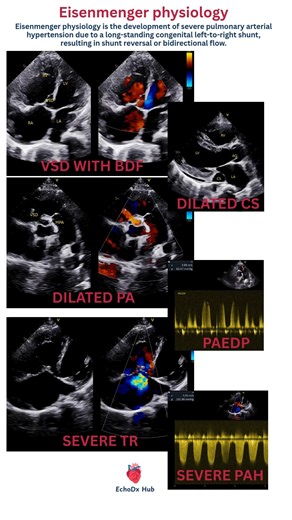

TR in 2 D Echo - Apical Aneurysm